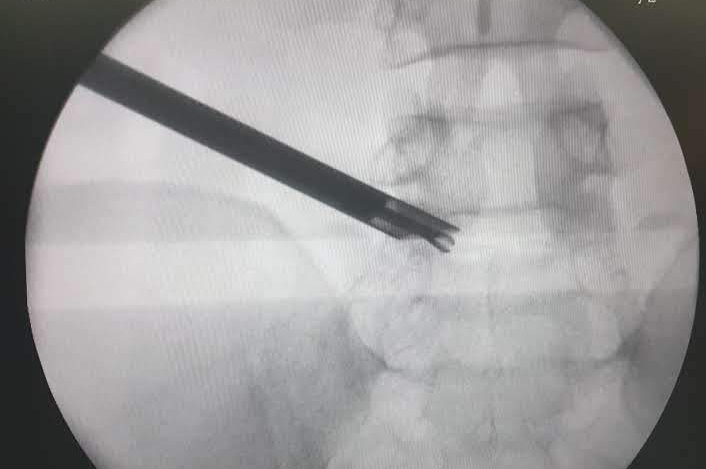

Endoscopic discectomy is a relatively new procedure in which the prolapsed disc fragment is removed through an endoscope introduced into the spinal canal through a keyhole of 7mm to 9mm size on the back. It involves much less muscle damage and no bone removal as compared to the conventional microscope assisted discectomy. It is usually done under local anaesthesia and has a quicker recovery time. The immediate postoperative pain is much lesser that the conventional disc surgery.